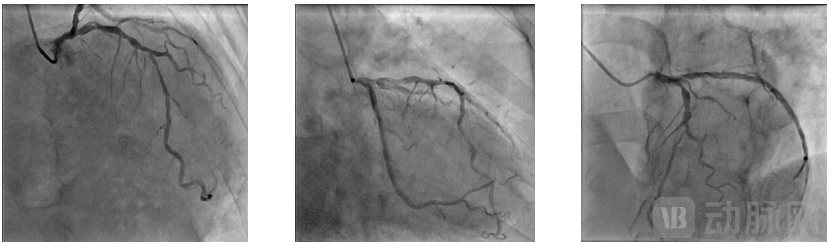

经评估,决定对该患者行高压三导丝刻痕球囊导管系统PCI介入术。经右侧桡动脉行冠脉造影,造影结果显示患者右冠优势型,前降支近段弥漫性病变,最重狭窄70%,前降支中段弥漫性病变,最重狭窄85%伴钙化,长度约30mm,直径3mm,TIMI血流III级;左回旋支近段、中段见支架影,支架内轻度内膜增生,未见再狭窄;左室后支中段狭窄70%;后降支开口狭窄95%,后降支中段狭窄70%。

介入治疗靶病变为前降支中段,6F EBU3.5指引导管送至左冠口,将导丝分别送至前降支及第一对角支远段,于前降支送入OCT导管回撤行OCT检查可见脂质斑块,最小管腔面积为1.9mm²,遂决定进一步行前降支介入治疗。术中使用Scoreflex TRIO 2.5*15m球囊于病变处以8atm*10秒扩张,复查造影残余狭窄改善明显,残余狭窄小于30%,TIMI血流III级;于病变处植入支架一枚以10atm*10秒扩张释放,取非顺应性球囊于支架内16atm*10秒后扩张塑形,复查造影提示支架扩张满意,无残余狭窄,远端TIMI血流III级。